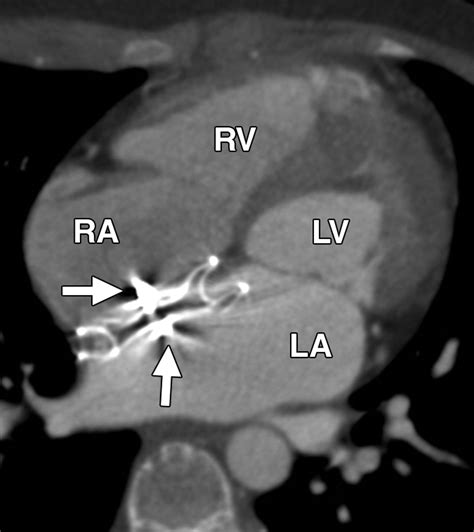

The Amplatzer Septal Occluder is specifically designed to address this by sealing the defect. It is essentially a self-expanding, double-disk device made from a flexible nitinol wire mesh. Once placed, it creates a "sandwich" effect that covers both sides of the hole, allowing the patient's own tissue to grow over the device over time, effectively healing the septal wall.

• Deployment: The Amplatzer Septal Occluder is pushed through the catheter. The left atrial disk is deployed first to anchor the device, followed by the right atrial disk.